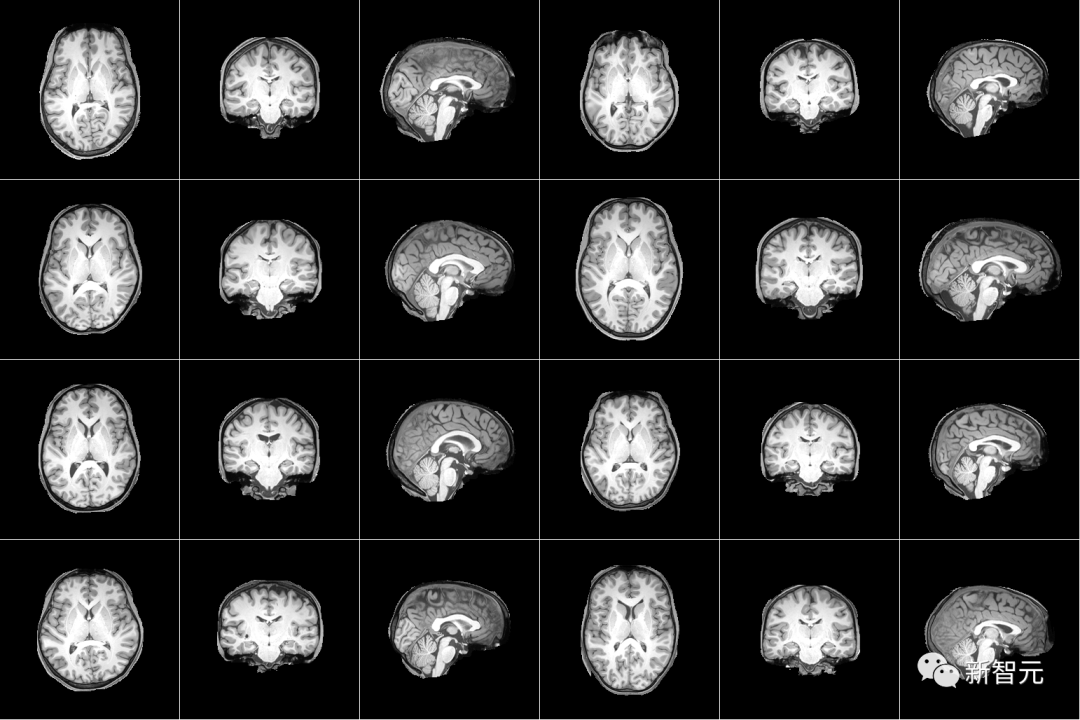

从MEG信号中生成图像

虽然将解码作为检索任务会产生很好的结果,但它要求正样本图像必须在检索集中,这在实践中的应用很有限。为了解决这个问题,作者训练了三个不同的大脑模块来预测。

根据表格1中的评估指标,生成的图像在视觉上表现出相对较高的质量,多个生成的图像正确地呈现了语义类别。然而,这些生成的图像似乎包含来真实图像的低级视觉信息。